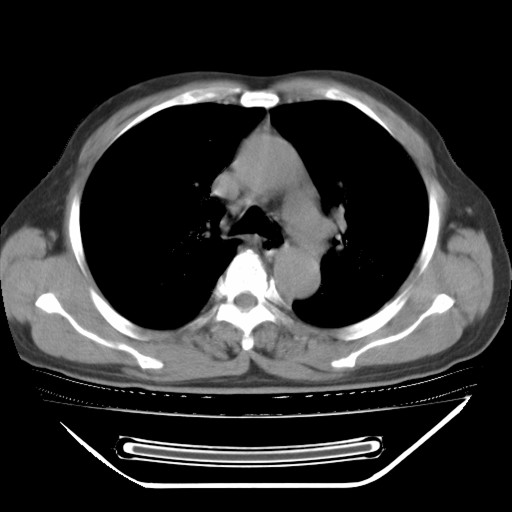

以下是引用hhcckk在2009-5-29 10:34:00的发言:[br]左下肺片絮状边缘模糊影,考虑感染,建议治疗后复查[br]